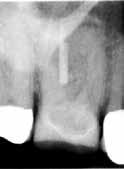

Fig. 15. Patienten blev (uden henvisning) opfordret til at fortsætte behandlingen på universitetstandklinik. Privatpraktiserende tandlæge havde påbegyndt rodkanalbehandling. A. Præoperativ røntgenoptagelse viser rodfyldt mesiofacial kanal. B. Klinisk foto efter fjernelse af midlertidig fyldning viser rodfyldning af MB1 og MB2 kanaler, furkal perforation (pil), instrumenteret distofacial kanal og palatinal kanal, som ikke er instrumenteret/fundet. C. Den furkale perforation blev lukket (pil), og den palatinale kanal blev lokaliseret og udrenset.

Fig. 15. Patient was advised (with no referral) to continue treatment at the University Dental Clinic. First maxillary molar had root canal treatment initiated by private practitioner. A. Preoperative radiograph showing root filled mesio-buccal canal. B. Clinical photo after removal of temporary restoration showing root filled MB1 and MB2 canals, furcation perforation (arrow), instrumented disto-buccal canal and uninstrumented/unlocated palatal canal. C. Furcation perforation was repaired (arrow), palatal canal located and instrumented.